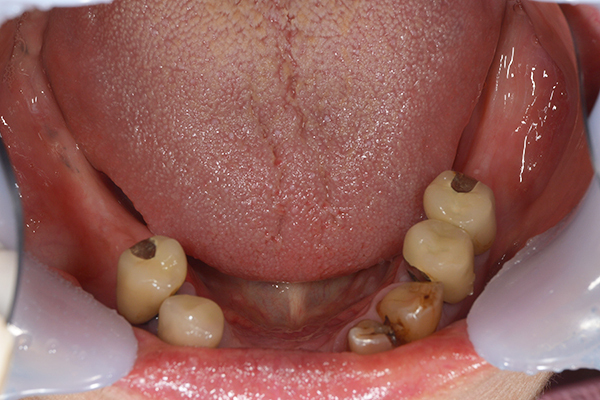

ケース5(金属使用 部分床義歯)

入れ歯をなくしてしまったので、あたらしく作りたい患者様です。

お口に入っている状態です。嘔吐反射が強かったため、うわあごの部分をくり抜いて作っています。

そのためにはしっかり歯に維持力をかける事、歯茎の部分に圧をかけるため、金属をつかって入れ歯を作成しました。

年齢 80代・女性

主訴 入れ歯をなくしたのであたらしくつくりたい。

治療期間 1ヶ月

治療費 義歯:330,000円(税込)

治療方針 以前作った入れ歯は気に入っていたが無くしてしまったとのことで、作り直しました。

上には残っている歯がありますが、入れ歯がない状態が続くと、歯へのダメージが強いことが考えられましたので、急ピッチで作っていくことにしました。

治療内容 入れ歯をつくるための前処置はとくに必要なかったため、すぐに入れ歯を作成していきます。

嘔吐反射が強く、普通の上顎の入れ歯を入れた時の違和感が強いため、口蓋部をくり抜いてつくっていきました。

そのため、歯や粘膜に維持負担を強くかけるため、金属を使用していくことにしました。

患者さんのお話をきいていると、前の入れ歯もそういう入れ歯をつくっていたとのことでした。

特記事項 入れ歯は完成してからがスタートです。入れ歯が歯ぐきにこすれて痛みが出る事が多いです。

今回の様な入れ歯ではそういう事が必ずと言っていいほどでます。

そのため、しっかり痛みをとるために入れ歯を調整して、患者さんに合わせた入れ歯にカスタマイズして完成になります。